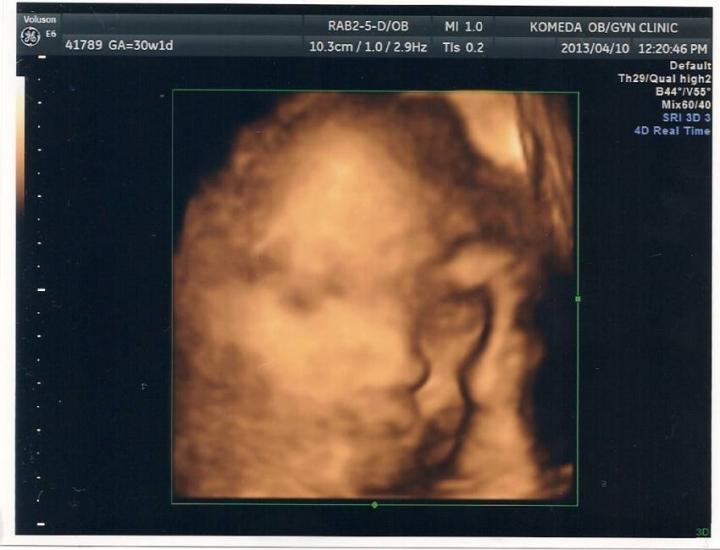

そして 初 4D!!

なぜか 頭を抱えています(笑)

頼りないお母さんかな(笑)

いつもどこの部位かわからないエコーだったので 初めて どこの部位かわかるのがもらえてよかった(^^)

体重も 推定1,500g